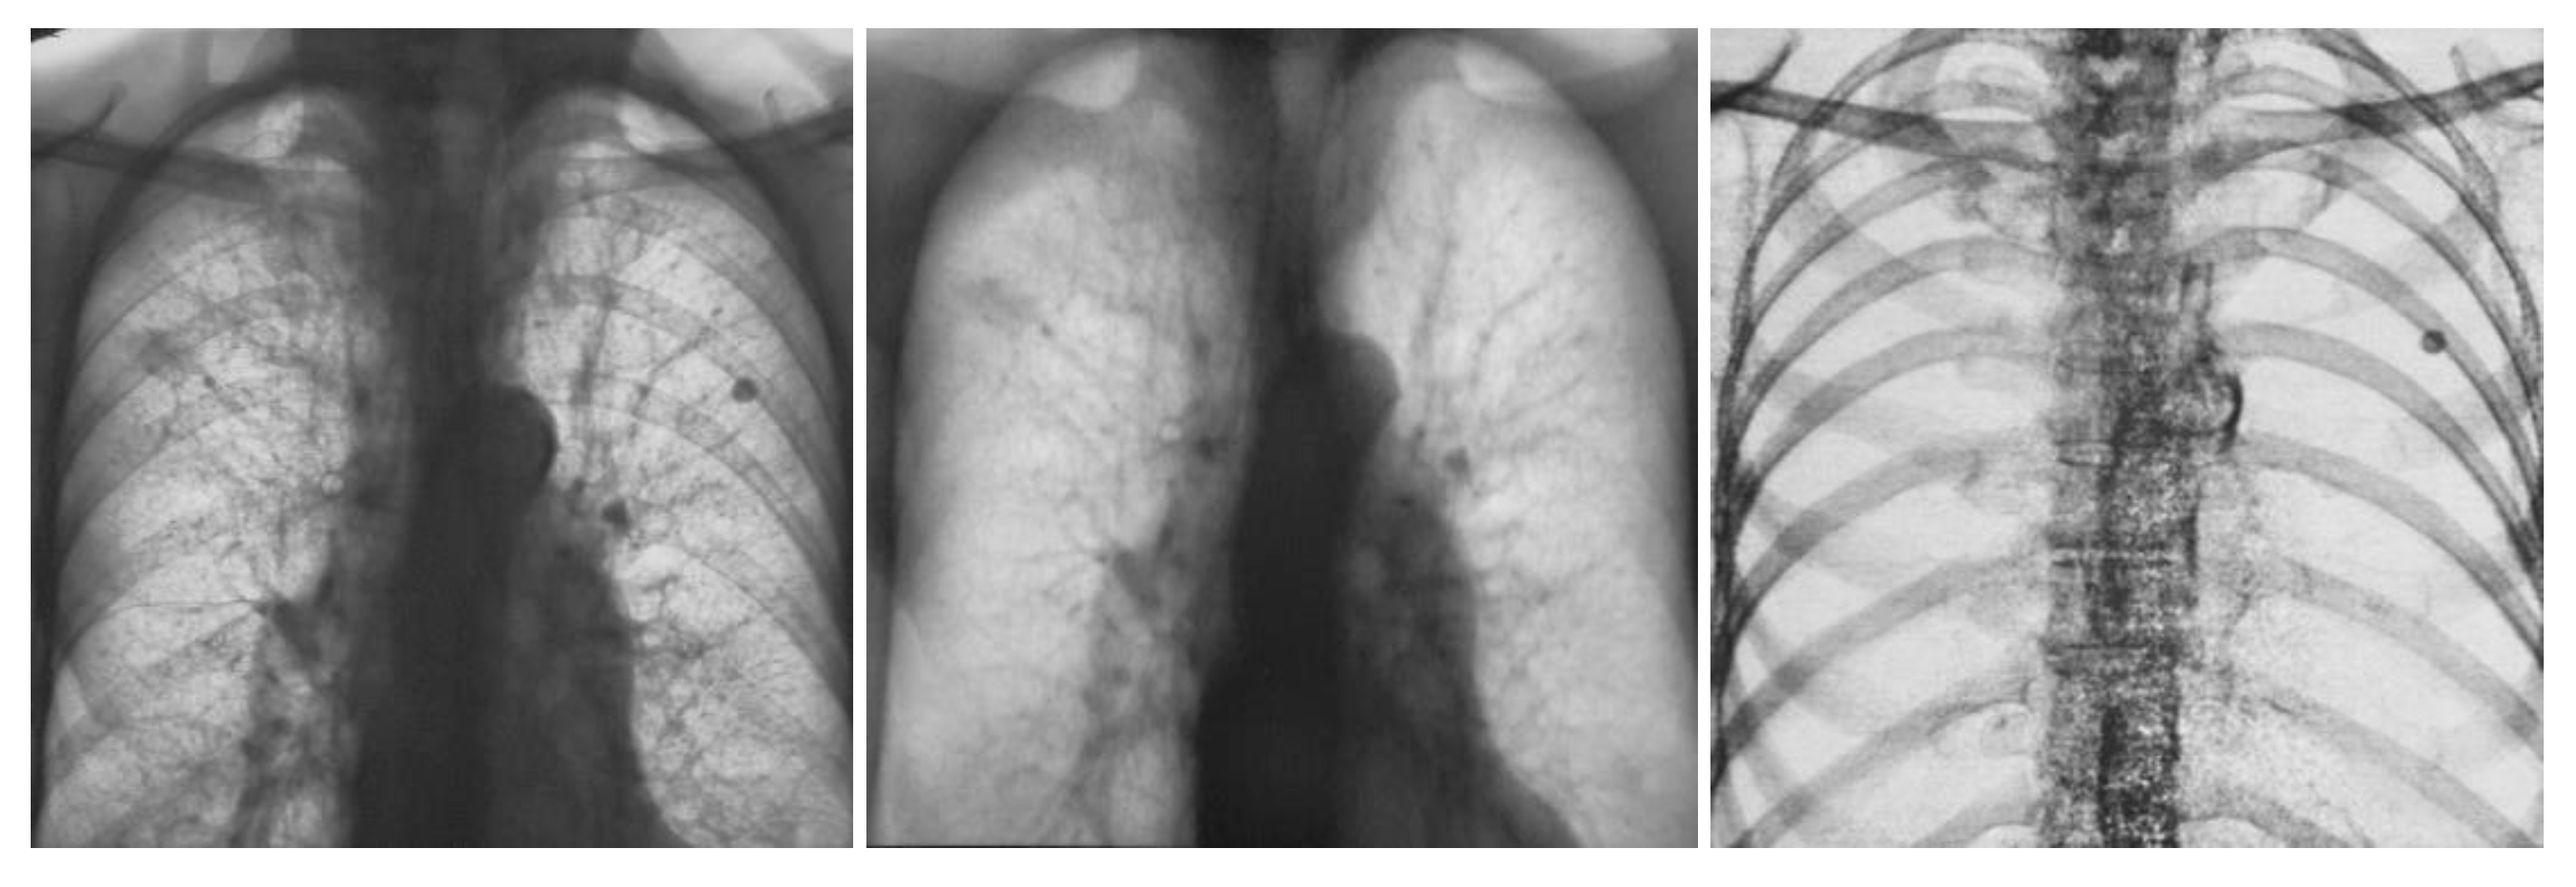

The application of CAD and radiomics to dual-energy X-ray imaging has not been adequately studied. Dual-energy chest radiography and more recently dual-energy or spectral CT have become commercially available and are routinely employed at many large medical centers. Advances in spectral CT are anticipated with the recent commercial introduction of photon counting CT. As illustrated in Figure 6 and Figure 7 dual energy chest radiography permits one to obtain a conventional digital chest radiographic image as well as additional subtraction images with the bones removed (soft tissue image) and with the soft tissue structures removed (bone image). With this capability, the radiologists’ ability to detect subtle pulmonary nodules improved as well as their ability to discriminate between benign and malignant lesions [124,125]. It is anticipated that spectral imaging will also improve the power of CAD and Radiomics when applied to three or more distinctly different images of the same anatomical structures rather than to a single image. Dual-energy or spectral imaging compared to conventional single-energy X-ray imaging also provides reliable quantitative information that could be used to reduce false positives. It is likely that Radiomics will also benefit from the accurate and reproducible quantitative input that spectral x-ray imaging provides.

Figure 6.

Images obtained on a prototype dual energy digital chest radiographic unit at the University of Alabama Birmingham circa 1985 with a single exposure: the conventional digital image was obtained by adding the low and high energy images (left); soft tissue image (center) and bone image (right) [124,125].

Figure 7.

Images obtained on a prototype dual energy digital chest radiographic unit at the University of Alabama Birmingham circa 1985 with a single exposure of a patient with lesions present in both sides of the lung in the conventional digital image (left); Soft tissue (center) and bone (right) images of the patient. The nodule in the lung left side is calcified and benign. The nodule on right side is present in the soft tissue image and not in the bone image, was not calcified and was cancer [124,125].